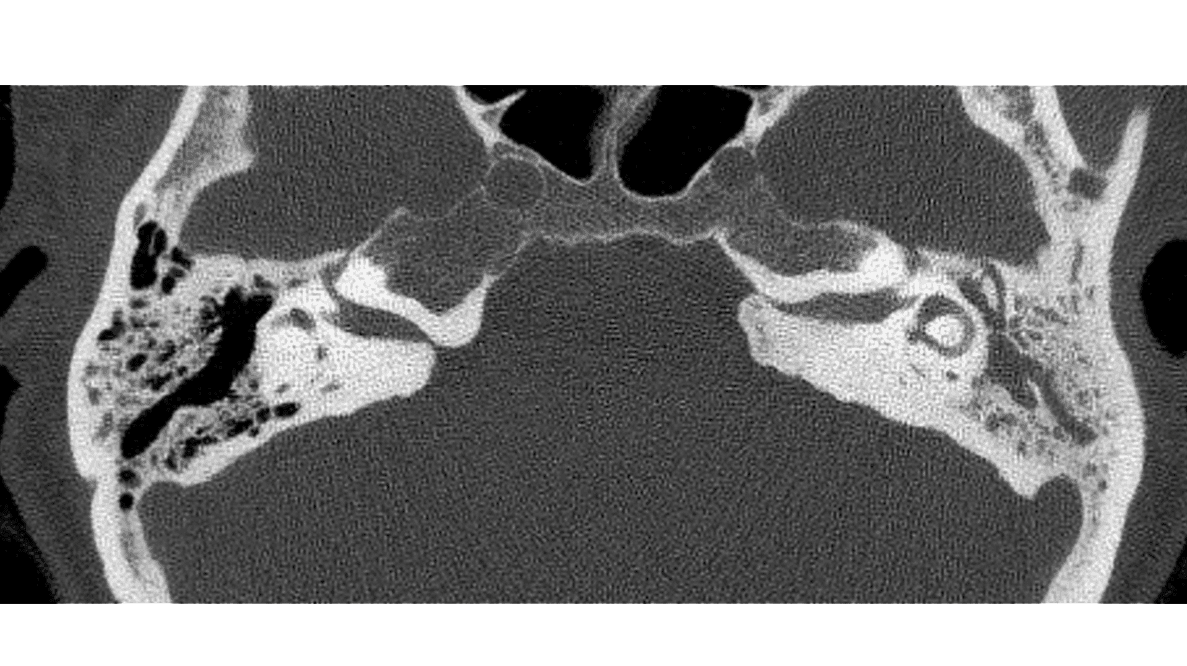

Supplerende CT af os temporale havde vist IAC-eksostose på begge sider (Figur 1 B + C) samt delvist sklerotiske venstresidige mastoidceller (II) med effusion i både mellemøre og mastoid.